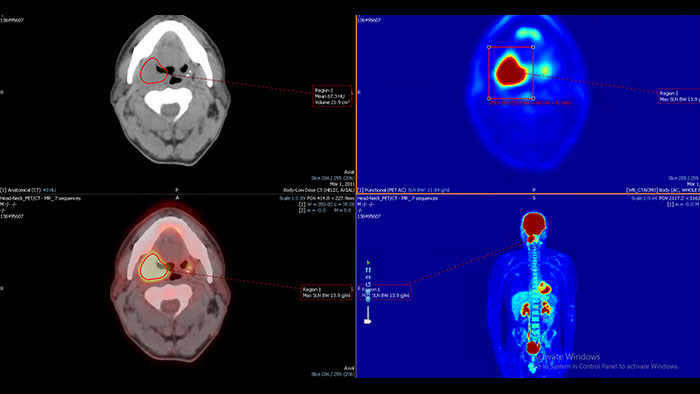

Enhanced user experience for NM reading with a leading NM viewing solution

A comprehensive NM solution, designed to enhance productivity of PET/CT and NM reading. It offers a solution for handling multiple studies requiring rigorous quantification of MV data**.